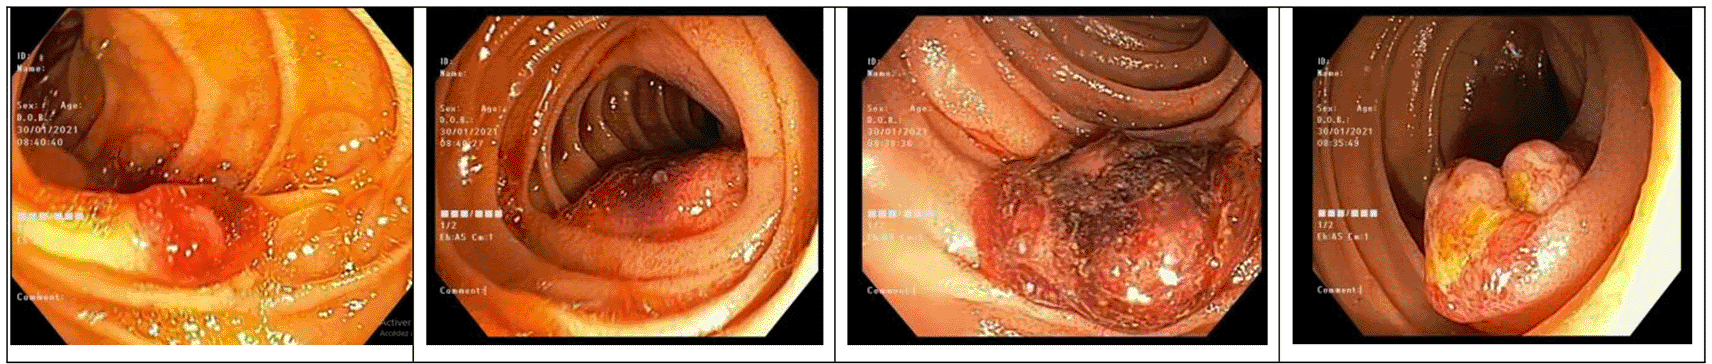

Esophagogastroduodenoscopy and duodenoscopy revealed multiple purpuric and hemorrhagic nodules of the ampullary region, the duodenal bulb and the duodenum, with a size ranging from 5 mm to 10 mm in diameter (Figure 1). A subsequent jejunoscopy showed multiple other erythematous and purpuric nodules and masses, some of which were bleeding. A colonoscopy was performed with no exceptional features noted.